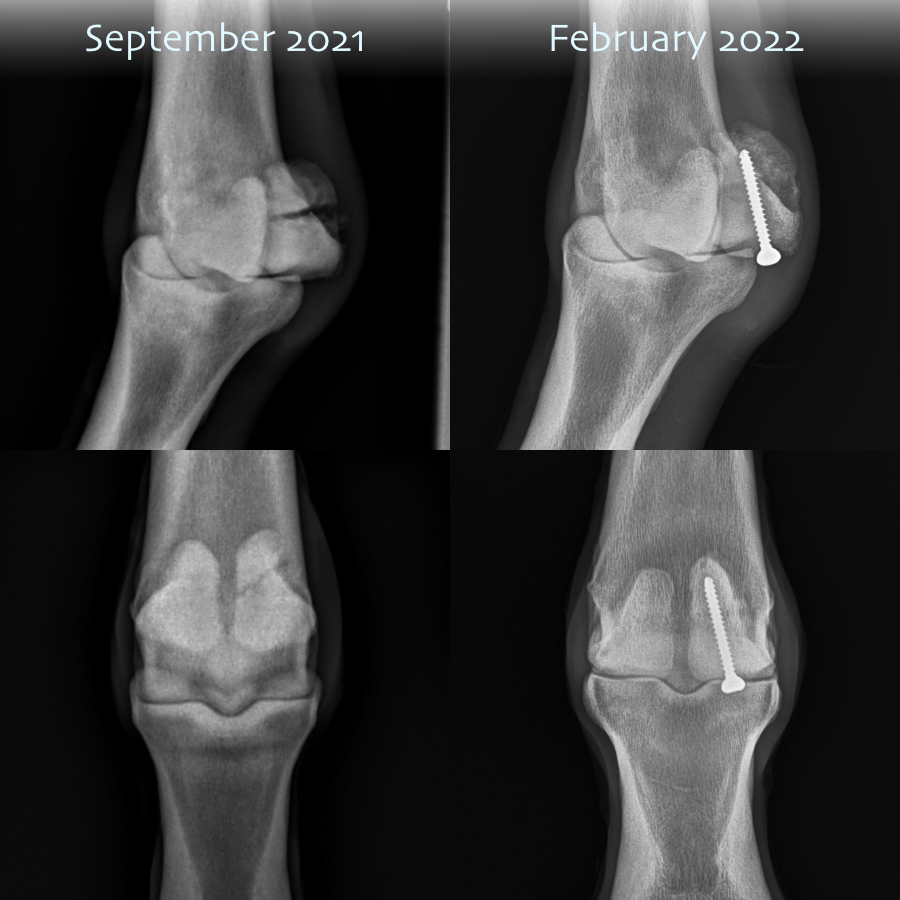

Cruz’s x-rays, September to February comparison

As I noted on my social media, some of the comments from Tufts veterinary team have revolved heavily around how well this very distal injury healed up. The latest set of x-rays showed that Cruz has minimal arthritic changes in the joint, with absolutely no debris - which two vets commented on separately. Additionally, her bone density is incredibly good, and she’s moving remarkably free on her front legs. In short, some incredible feedback and a wonderful outcome for my wonderful girl!